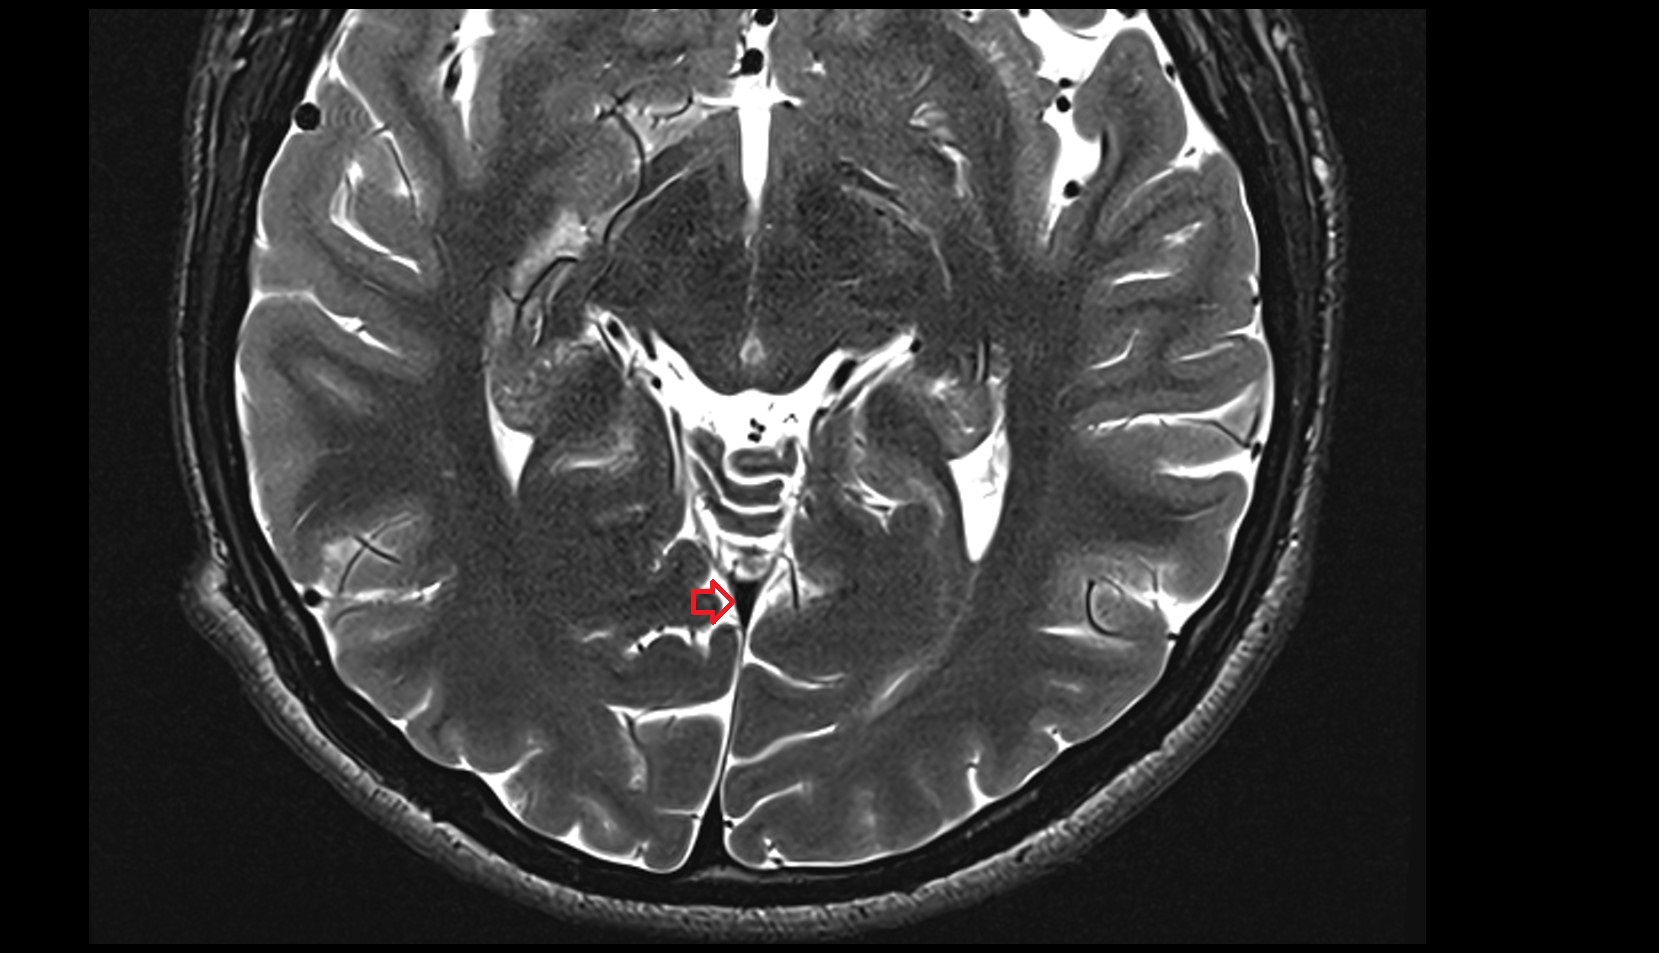

- Lateral aperture of fourth ventricle (foramen of Luschka)